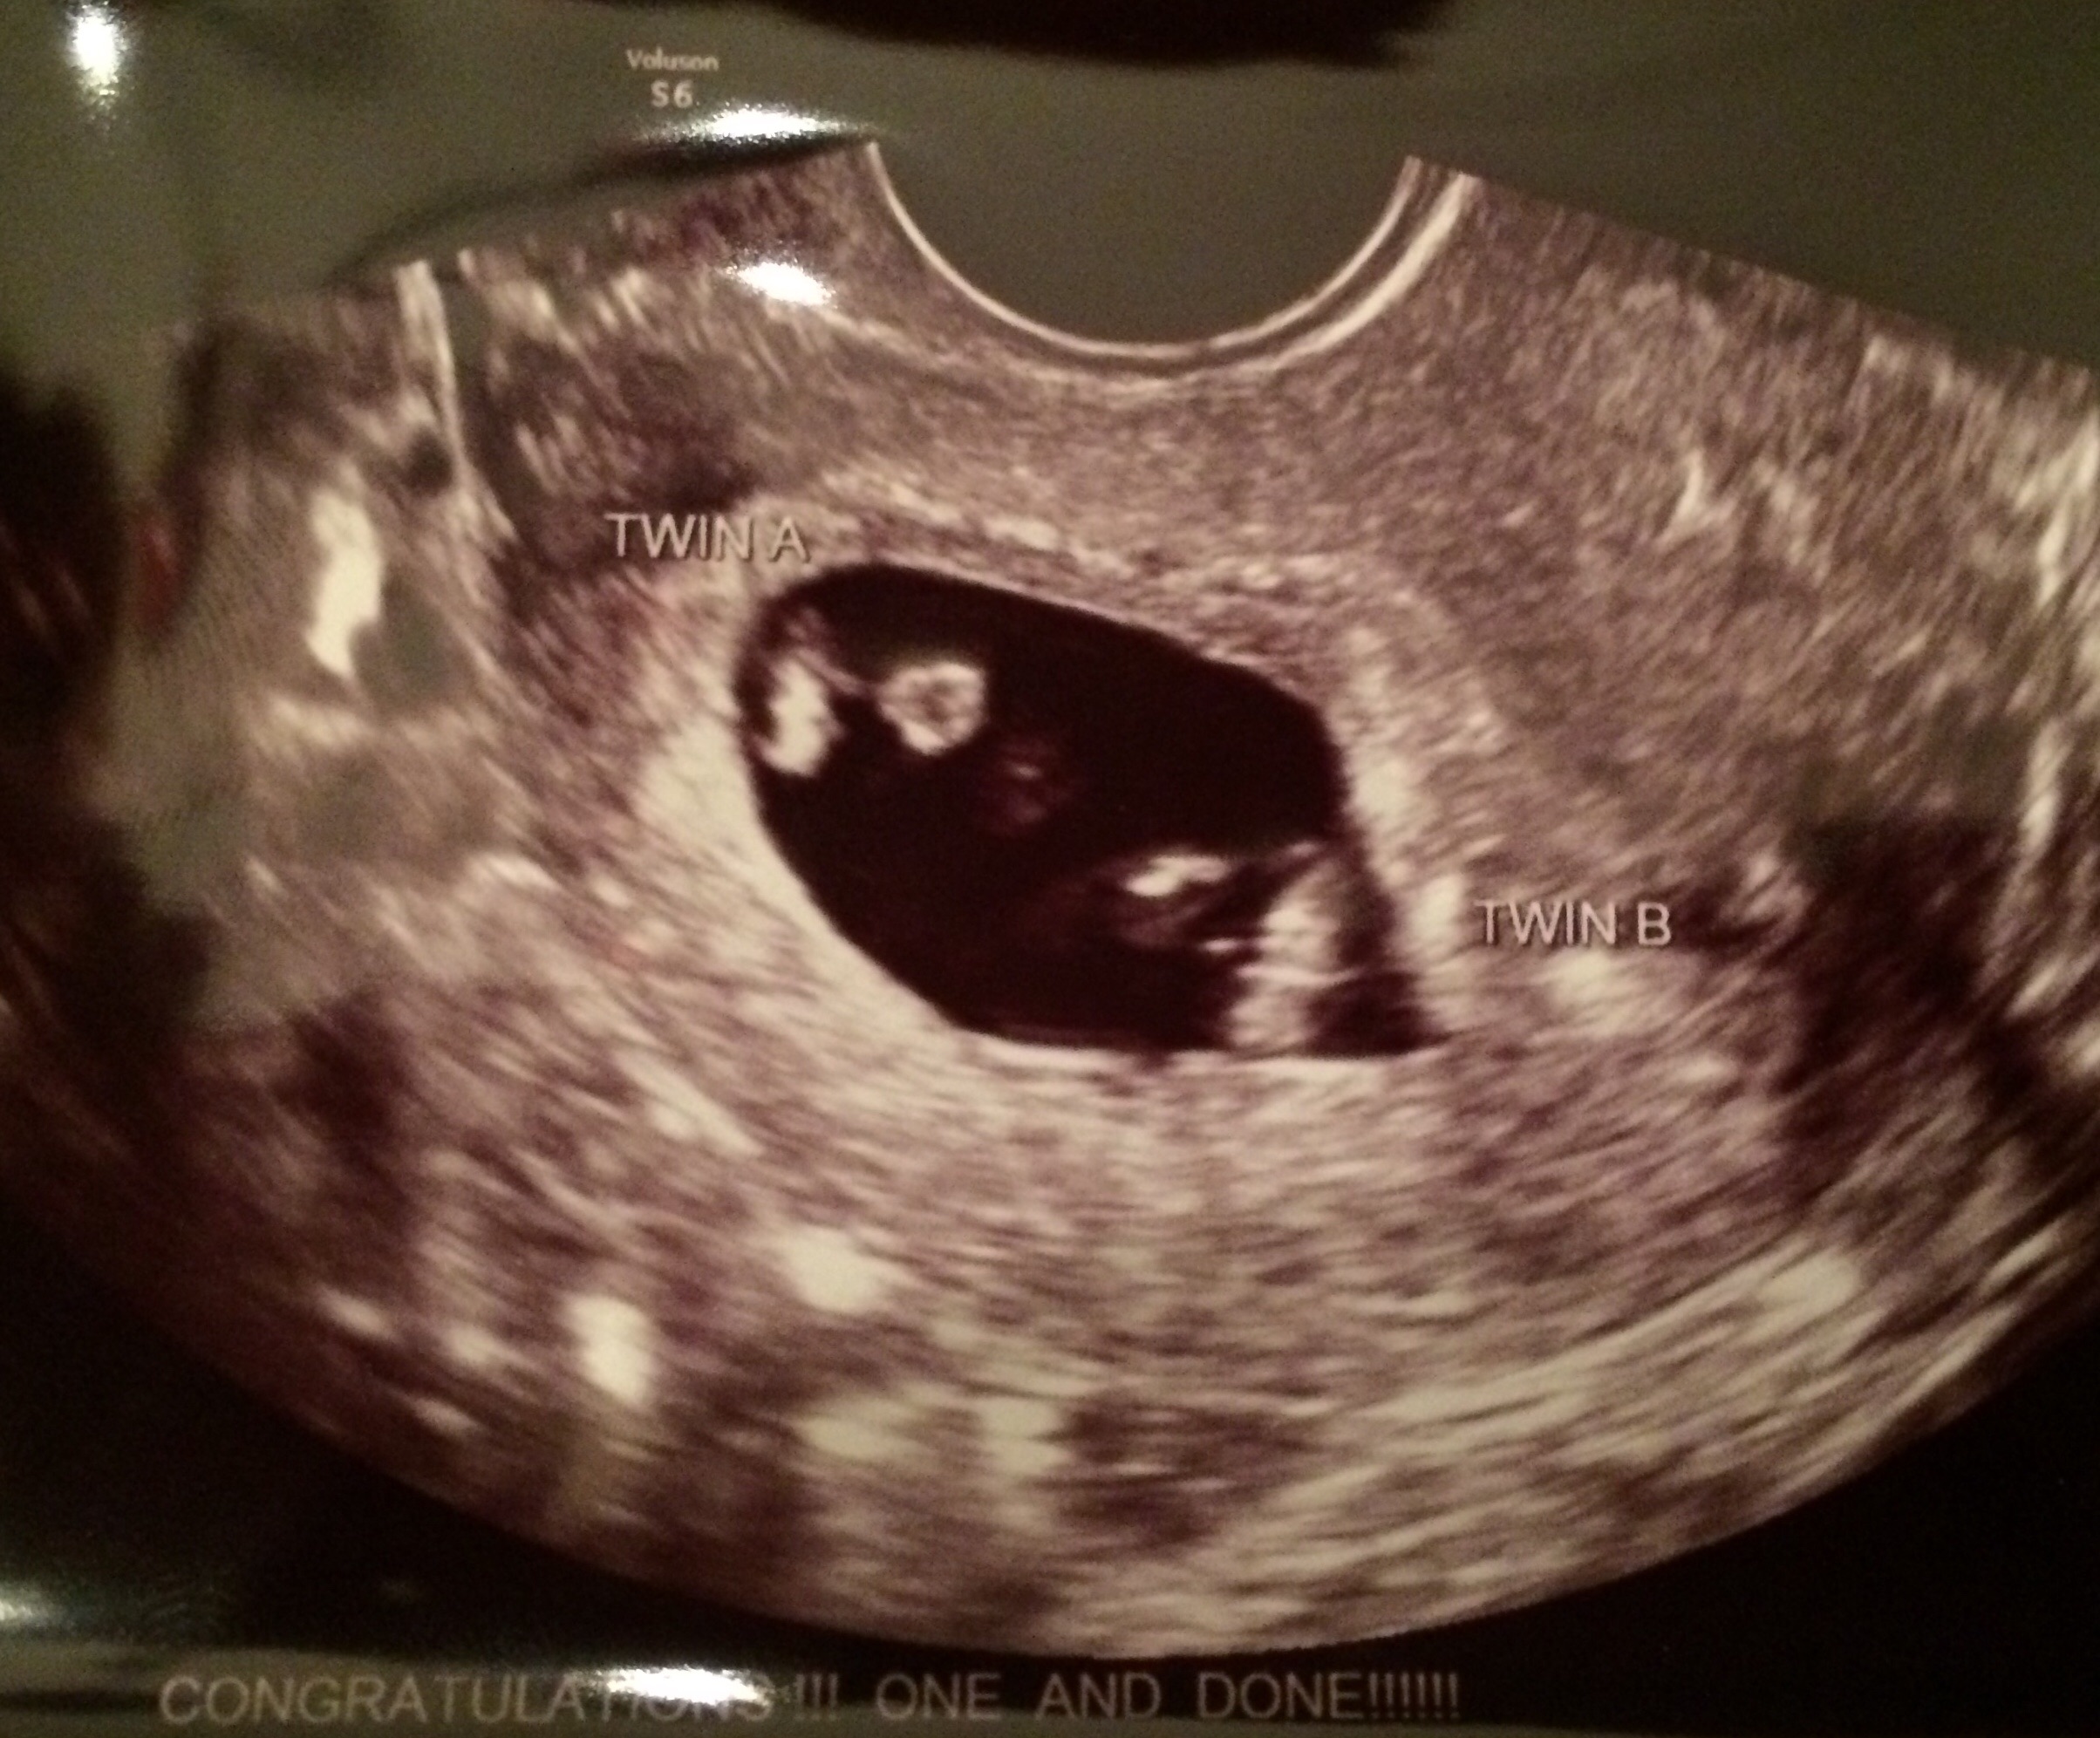

Hi girls! Newish to this board. Been browsing a lot but haven't commented on anything yet! Mostly still can't believe that I am pregnant!!! Had some spotting issues over the weekend. Nothing serious- just very brief and light in color. They did a sonogram on me and everything was just fine.... with BOTH of the babies... What!?! There are two? Now I am into a whole new world of shock and worry and sometimes excitement. Just mostly disbelief.

• Honestly. I don't even know if they are identical or did I even ask if they were sharing a sac!!! I was in shock!?! I'm no sonogram reader but I was wondering if that was what was going on! Have an appointment in two week. Will need to ask more questions then!!!

I'm no expert on twins but I did research twins the other day because @irishtheatrechic‌ has a rare set of identical twins. The few ppl I know that did IVF and has twins you can see 2 sacs and your us looks like there is only 1.

• I believe they are identical looks like only one sac

The only way to know your twins are identical in the womb is when they are MoMo (monochorionic and monoamniotic) and share the same sac and share a placenta. Otherwise you will have to confirm with a blood test when they are born.

• Congrats from one twin mom to another! It looks like there may be a membrane between the two, but I'm no expert. Join us on the Twin Tuesday check in, and don't hesitate to ask any questions. I'm 12w3d and still learning as much as possible.